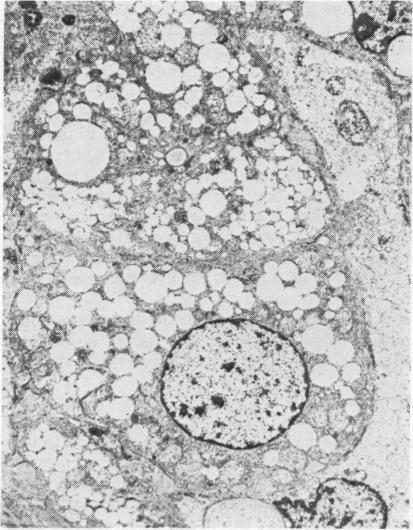

Three children with Reye's syndrome are described. One child died, the second had mild and transient illness, and the third had recurrent episodes. In all 3 children a muscle biopsy showed pronounced infiltration of the myofibres with fat microdroplets as shown by the oil red O stain and by electron microscopical examination. We suggest that needle biopsy of muscle may be a quick and safe aid to the diagnosis of Reye's syndrome, and may be preferable to liver biopsy in view of the pronounced tendency to bleed in Reye's syndrome.

本文描述了3例患有瑞氏综合征的儿童。1例儿童死亡,第2例病情轻微且为一过性,第3例有反复发作。所有3例儿童的肌肉活检均显示,油红O染色及电子显微镜检查表明肌纤维有明显的脂肪微滴浸润。我们认为,肌肉穿刺活检可能是一种快速且安全的辅助诊断瑞氏综合征的方法,鉴于瑞氏综合征有明显的出血倾向,肌肉穿刺活检可能比肝脏活检更可取。